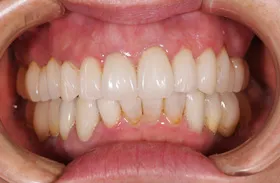

矯正及びインプラントで治療のケース

矯正により歯の位置を適正な位置に動かし、歯の無い部分に対してインプラントにより回復したケースです。

■治療後3

上下とも美しい歯並びと噛み合わせになりました。 形だけでなく、色みも自然な仕上がりです。

| 主訴 | 下の歯が1本無いので歯ならびが良くなく、かみ合わせも悪い |

| 治療方法 | 矯正治療+インプラント治療+補綴治療 |

| 治療期間 | 約3年 |

| 通院回数等 | 約35回 |

| 費用 | 約160万円 |

| リスク・副作用 | 矯正治療も行ったので治療期間が長くなった インプラント術後の腫れ・痛み |